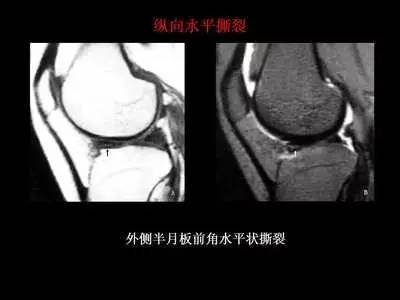

外侧半月板前角撕裂核磁影像